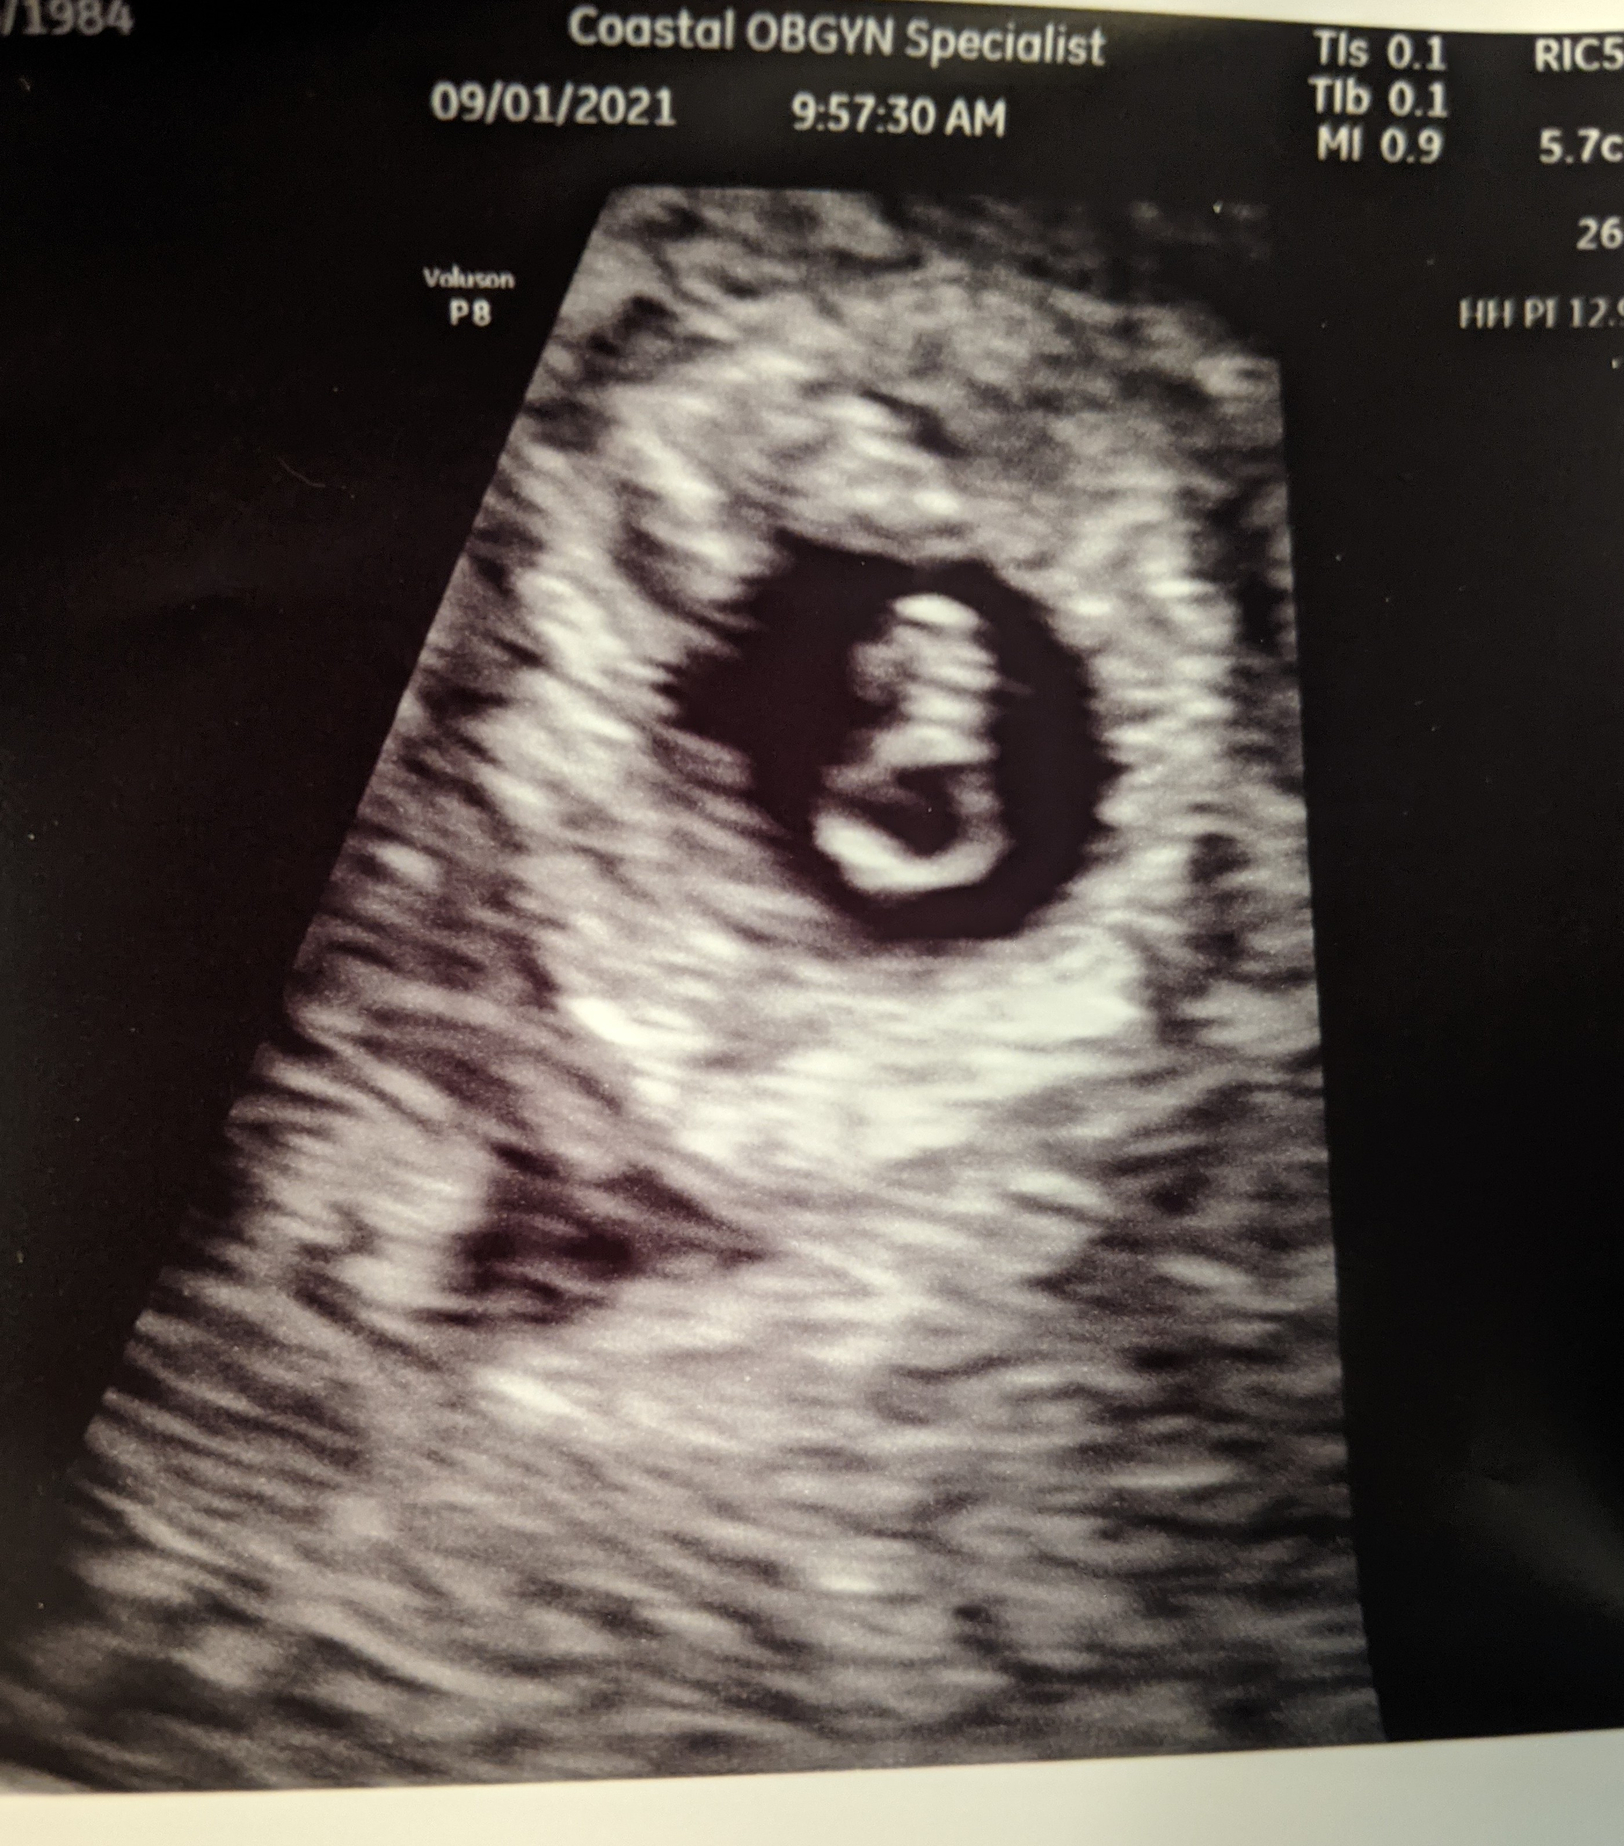

• 7w3d. First pregnancy. I started spotting Monday night, bleeding Tuesday morning. Went into my OB and my cervix was closed, ultrasound found a weak heartbeat. Blood test came back with 631 HCG. Went today for RhoGAM. They did another ultrasound today and the heartbeat was there but too weak to measure. Getting another HCG check tomorrow to benchmark, then I have to wait until next Tuesday…I’m just…. Broken…

• Just went in for my ultrasound today. Supposed to be 9w and she couldn't get a reading on the regular ultrasound, only a sac. She did the transvaginal and there is a fetus measuring 6 weeks but no heartbeat. She wants me to come back for another ultrasound in a week to see if there is any growth or changes. Has anyone had a similar situation that turned out ok? I'm trying to not worry but I'm not holding out much hope. There's no way my dates would be off by that much.